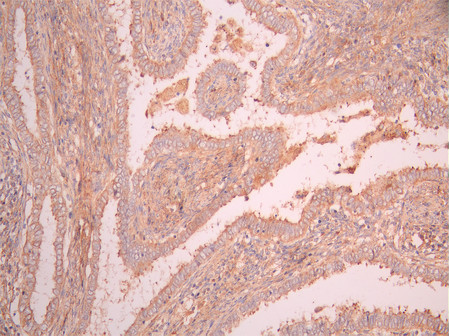

IHC image of CSB-RA964035A0HU diluted at 1:100 and staining in paraffin-embedded human tonsil tissue performed on a Leica BondTM system. After dewaxing and hydration, antigen retrieval was mediated by high pressure in a citrate buffer (pH 6.0). Section was blocked with 10% normal goat serum 30min at RT. Then primary antibody (1% BSA) was incubated at 4°C overnight. The primary is detected by a Goat anti-rabbit polymer IgG labeled by HRP and visualized using 0.05% DAB.

IHC image of CSB-RA964035A0HU diluted at 1:100 and staining in paraffin-embedded human endometrial cancer performed on a Leica BondTM system. After dewaxing and hydration, antigen retrieval was mediated by high pressure in a citrate buffer (pH 6.0). Section was blocked with 10% normal goat serum 30min at RT. Then primary antibody (1% BSA) was incubated at 4°C overnight. The primary is detected by a Goat anti-rabbit polymer IgG labeled by HRP and visualized using 0.05% DAB.